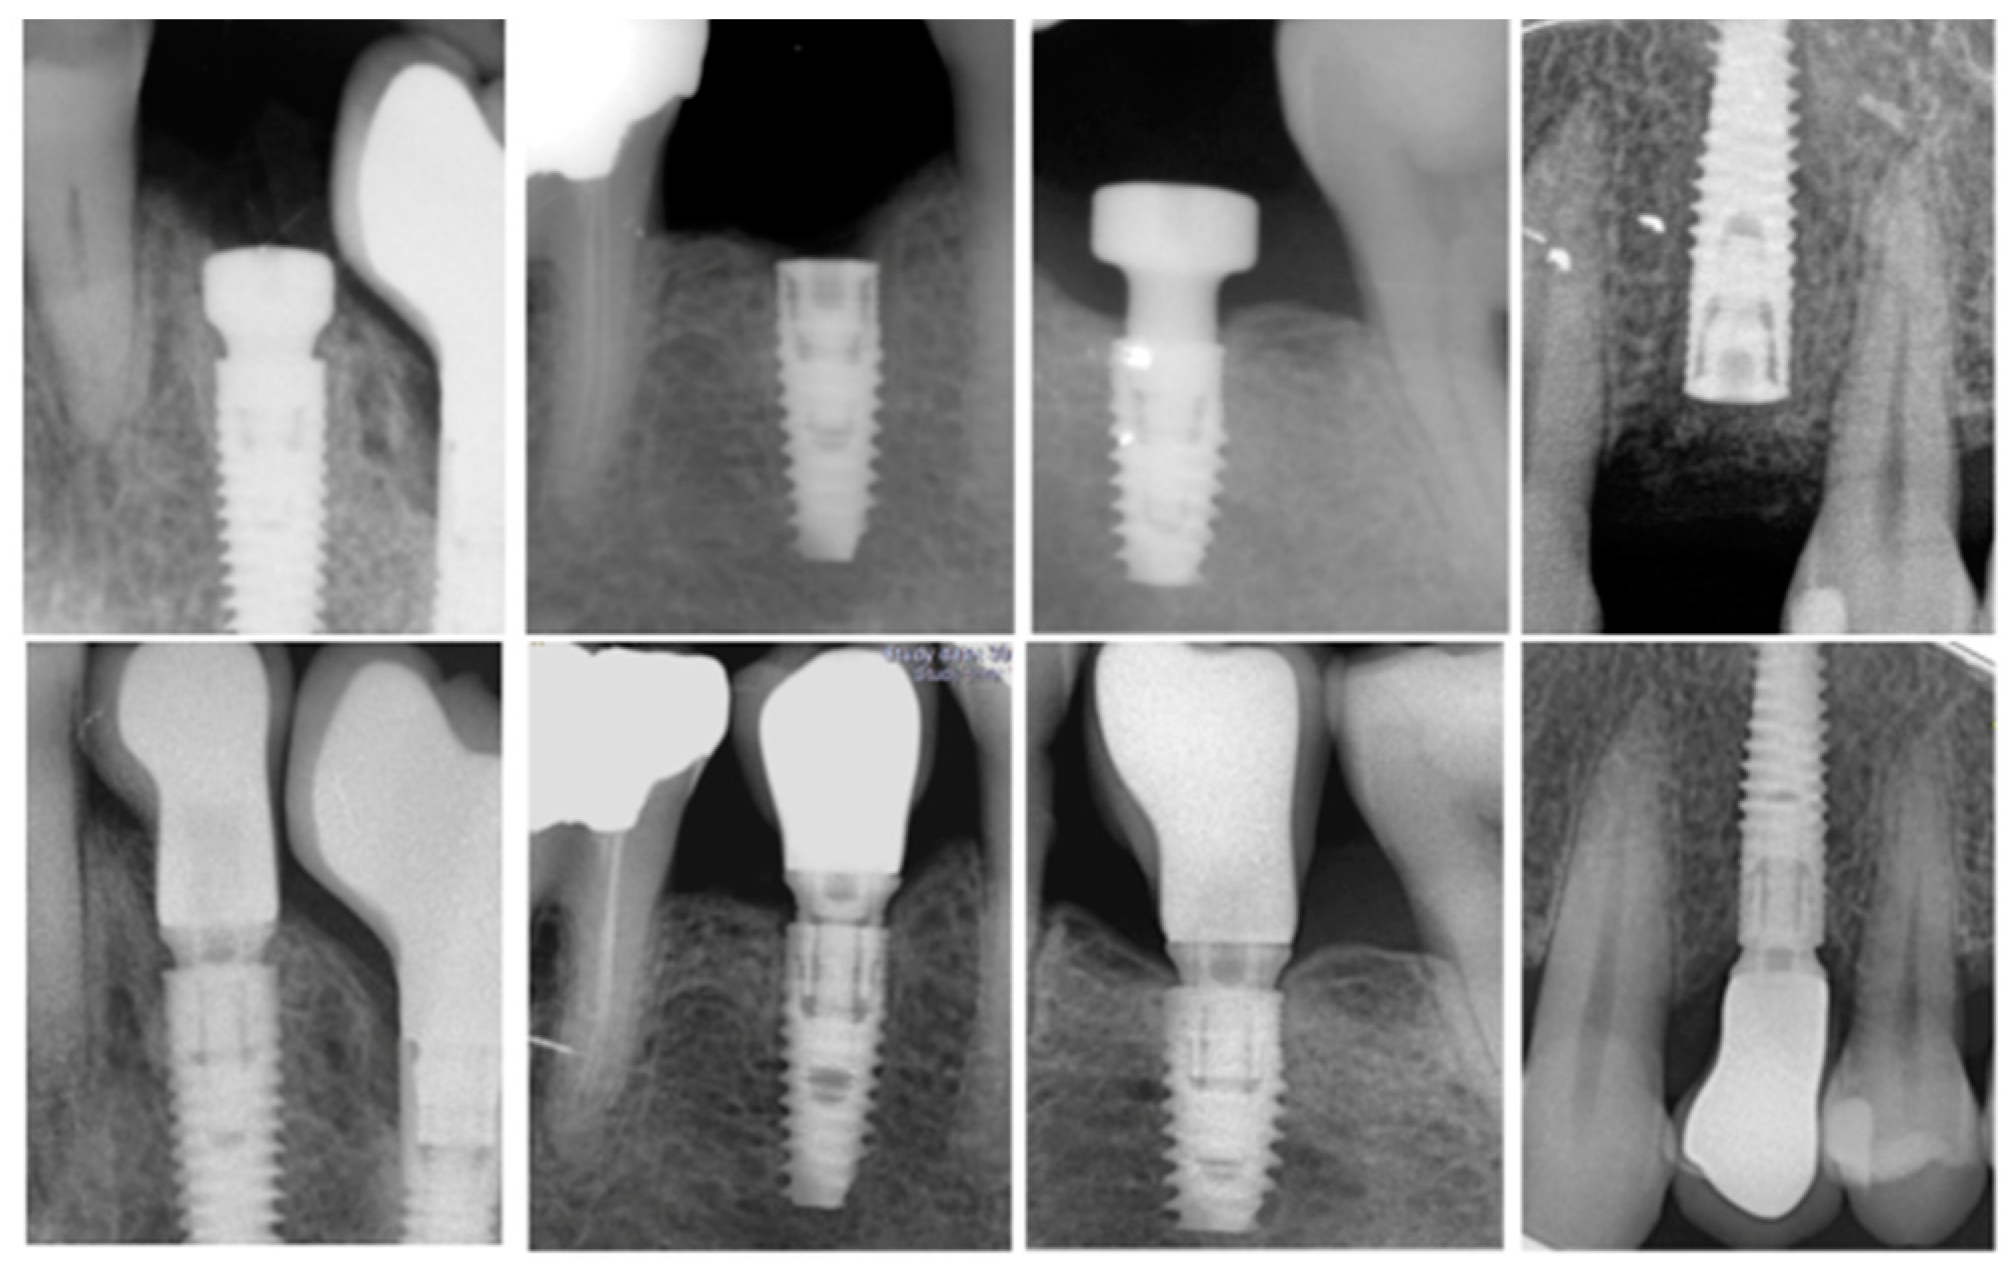

Periapical radiographs of each implant were acquired with an intraoral dental film using a plastic index according to the parallel technique immediately after implant placement, at prosthesis delivery, and at the 1-year follow-up. Measurements were performed with the Image J software (10.8.0_172, NIH, MD, USA); internal calibration was provided by the implant diameter at the neck level. At each time point, the distance from the implant shoulder to the first bone-implant contact was measured on the mesial and distal sites. The difference between baseline and the milestone served to calculate the MBL on each side. Subsequently, the mean value of the two measurements was calculated for each implant. (Figure 1).

Figure 1.

Periapical radiographs with an intraoral dental film using a plastic index according to the parallel technique for marginal bone loss (MBL) analysis between baseline and 1 year follow-up.